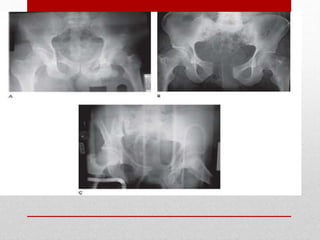

PELVIS

• Blunt injury to the pelvis may produce mechanically

unstable fractures with major hemorrhage.

• Plain radiographs will reveal gross abnormalities, but

CT scanning is necessary to determine the precise

geometry.

Pelvic

Fracture

Hemorrhage

Control

• These injuries often occur in

conjunction with other life-

threatening injuries, and there is no

universal agreement among

clinicians on management.

• Current management algorithms in

the United States incorporate

variable time frames for bony

stabilization and fixation, as well as

hemorrhage control by preperitoneal

pelvic packing and/or

angioembolization.

• IDENTIFICATION OF INJURIES

• PELVIC BINDER

• EXFIX

• PRE PERITONEAL PELVIC PACKING